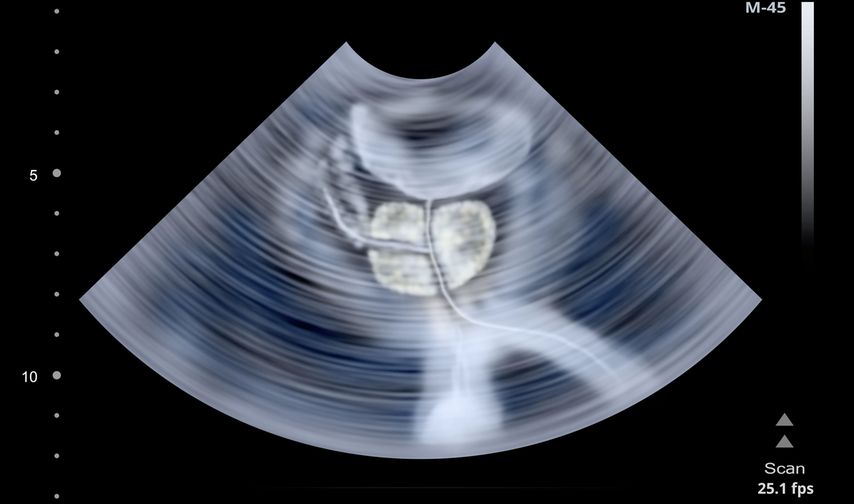

Bei Männern mit einem anfänglichen PSA-Wert von ≥3ng/ml wird nach zwei Wochen ein bestätigender PSA-Test durchgeführt. Bei einem konfirmierten PSA-Wert ≥3ng/ml besteht die Empfehlung einer multiparametrischen MRT (mpMRT) der Prostata und einer gezielten MRT-Ultraschall-Fusionsbiopsie mit systematischer Biopsie.

In der ersten Screeningrunde wurde bei 147 der 186 Teilnehmenden der Hochrisikogruppe (79,0%) das empfohlene mpMRT durchgeführt. 120 der 186 Männer (64,5%) willigten in die Prostatabiopsie ein. Bei 114 von ihnen wurde eine MRT/Ultraschall-Fusionsbiopsie mit einer zusätzlichen systematischen Biopsie durchgeführt, die übrigen sechs Teilnehmenden unterzogen sich lediglich einer systematischen Biopsie.